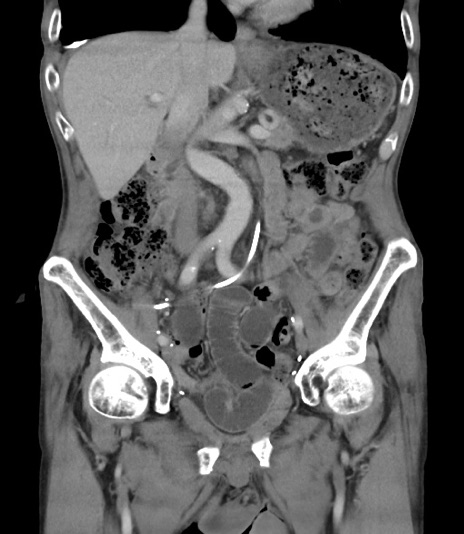

症例3(冠状断像)

【症例】 70歳代男性

【主訴】右鼠径部腫瘤、疼痛

【現病歴】本日朝より上記主訴あり、受診。

【既往歴】膀胱癌にて膀胱全摘、両側尿管皮膚瘻

【データ】WBC 5600、CRP 0.56